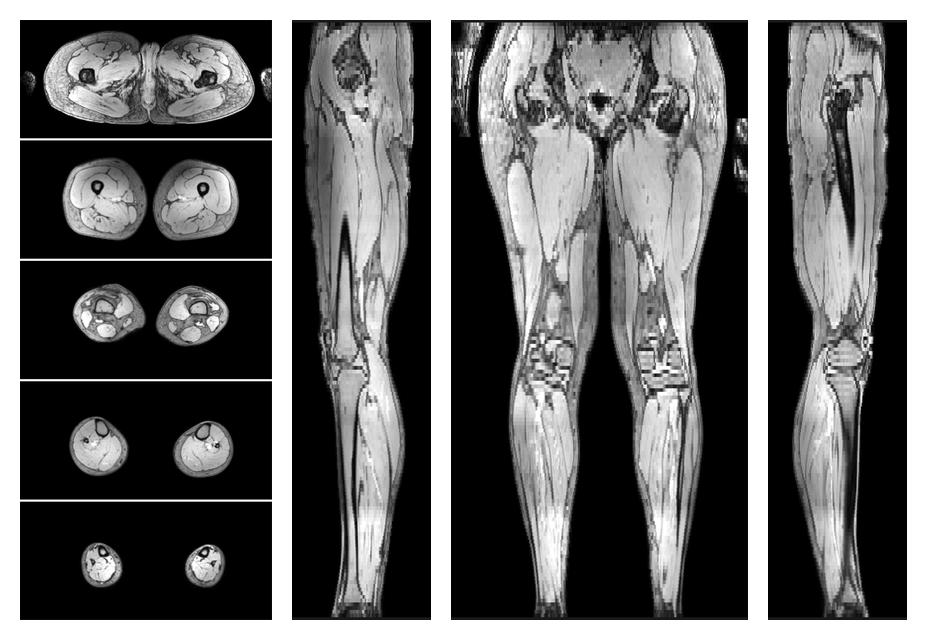

• Water only signal

The water part of the acquired multi-echo spin echo data.